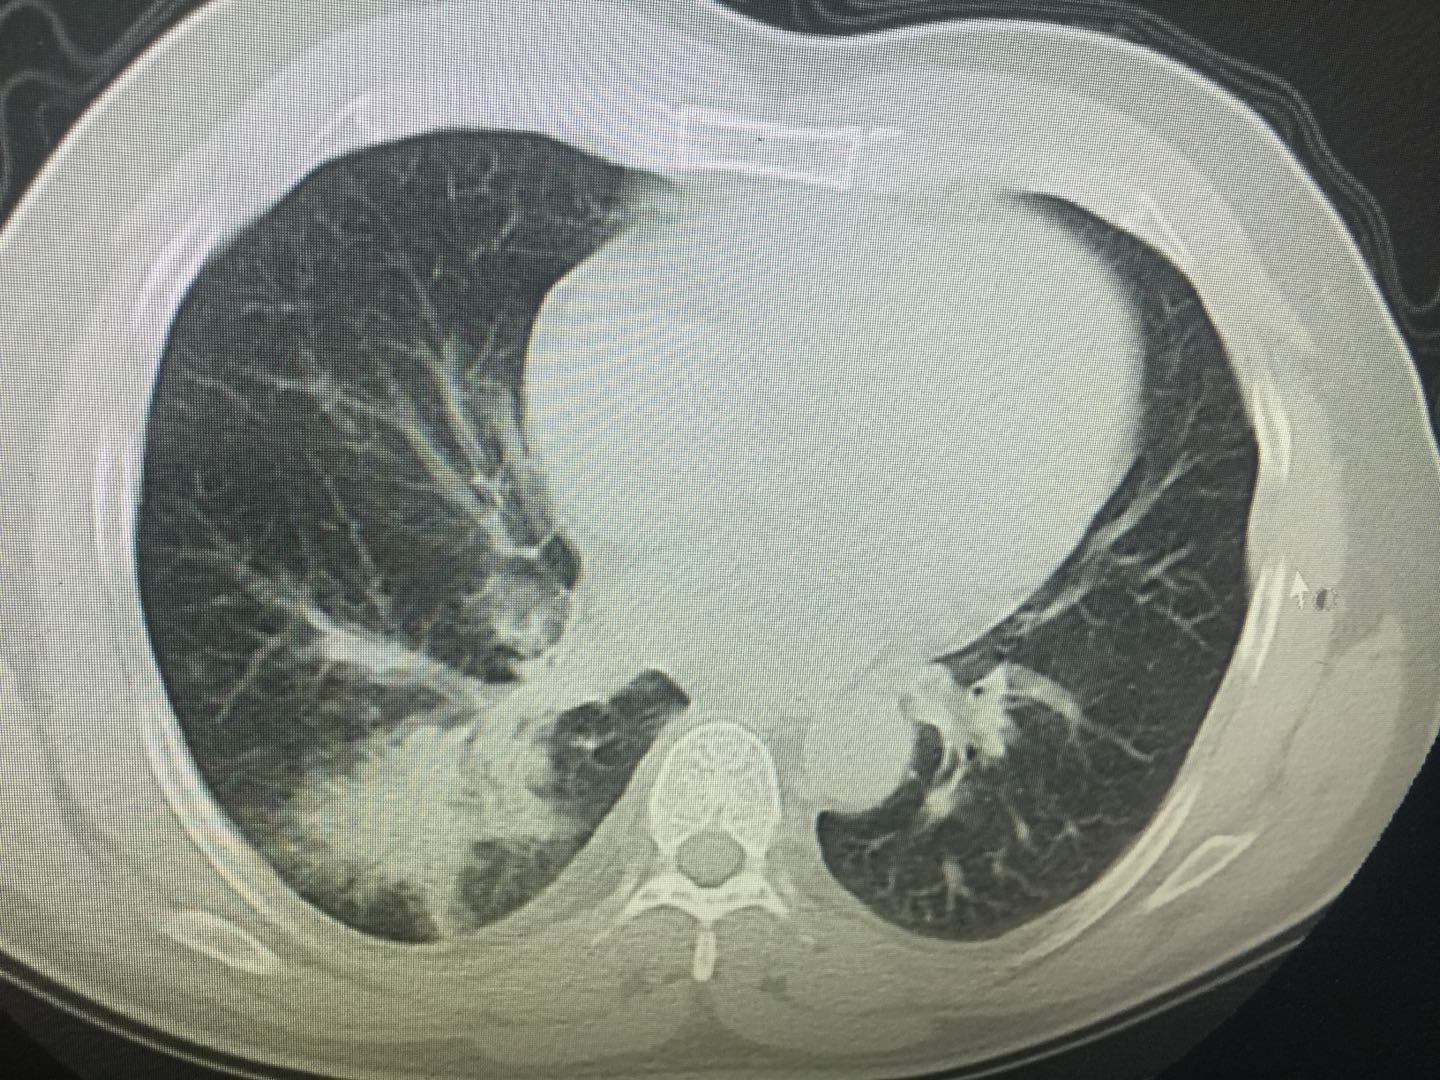

常见慢性支气管炎、肺炎、肺脓肿、支气管扩张、肺真菌病、肺癌等。患“老慢支”病人一般痰中血量小,但反复发作。肺炎、肺脓肿多起病急,有寒战高热伴胸痛,咳大量脓血痰,待病程结束后也可缓解。肺真菌病常见免疫力低下、长期使用抗生素的患者,咳嗽、血痰伴发热乏力,可以通过血清反应或发现真菌菌丝确诊。肺癌患者中,持续异常呛咳,伴咳血痰、咳血是早期甚至第一症状,及时就医,拍片排查有助于尽早发现癌症病灶。

如心衰、风湿性心脏病、二尖瓣狭窄、肺栓塞等疾病,心脏功能衰竭,肺部静、动脉及小血管高压,肺组织充血,会引起血管壁破裂渗血。肺心病特征为粉红色泡沫样痰,患者应注意坚持服用药物,控制血压、增强心肺功能及利尿排水,减轻心肺负担。急性肺栓塞除咳痰咳血外,患者还伴有胸痛、胸闷、烦躁多汗、呼吸困难等体征,及时拍胸片发现栓塞位置可以帮助抢救。